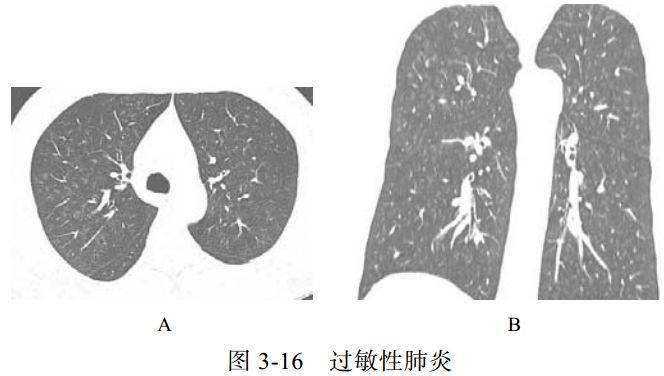

(二)过敏性肺炎

过敏性肺炎(HP)是由吸入各种抗原性有机物粒子而引起的弥漫性肉芽肿间质性肺疾病,分为急性期、亚急性期、慢性期(不同阶段可以重叠),组织学表现和影像学表现相似,与抗原类型无关

影像学表现:

(1)双肺多发边缘模糊的小叶中心结节(图 3-16)、磨玻璃样影

(2) 奶酪头征,后期纤维化

(3)吸气相加呼气相的 HRCT 检查有助诊断